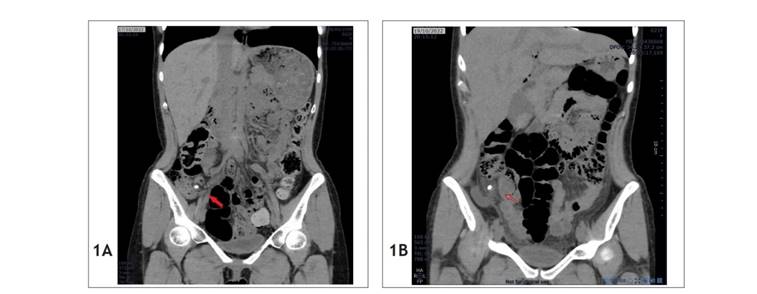

Se trata de un varón de 77 años de edad que ingresó el 16 de noviembre del 2021 (día 1) a emergencia de un hospital público de Lima. Se quejaba hace 4 días de un dolor en el hipogastrio; con antecedente de hipertensión arterial y colecistectomía. Luego de ser evaluado se llegó al diagnóstico clínico de apendicitis aguda, el cual fue corroborado por una TC que informó de los hallazgos (Figura 3A): "apéndice cecal engrosado en 17 mm con apendicolitos y burbujas de gas en su interior". Los exámenes revelaron sus leucocitos: 15 290/mm3. Entonces, se le programó una apendicectomía laparoscópica. Durante la operación, se evidenció un plastrón apendicular con asas intestinales friables, por lo cual se decidió convertir la operación a una apendicectomía abierta. Se realizó la liberación de adherencias, con apertura de la fascia de Told del parietocólico derecho, y se encontró un apéndice cecal de ubicación retrocecal, retroperitoneal, ascendente, necrosado en toda su extensión con mesoapéndice necrosado; se extrajeron 2 coprolitos a nivel de la punta del apéndice, con aspiración del absceso de 15 cc de volumen a ese nivel y apendicectomía. Se colocó un dren Penrose a nivel de muñón apendicular con salida por contraabertura. Se indicó en el posoperatorio ayuno por 3 días, ceftriaxona y metronidazol.

Durante su hospitalización posoperatoria, el paciente cursó con evolución favorable; en el cuarto día posoperatorio (día 5) se inició dieta blanda y al día siguiente (día 6), dieta completa, la cual toleró adecuadamente, con eliminación de flatos y heces. En el sexto postoperatorio (día 7), el paciente presentó eructos y distensión abdominal, por lo cual se le solicitó una TC (Figura 3B), que informó de los hallazgos: "asas intestinales delgadas dilatadas tanto en yeyuno como en íleon proximal con diámetro máximo de 41 mm, con varios niveles hidroaéreos, a descartar adherencias. Llama la atención a este nivel una imagen hiperdensa suelta en grasa peritoneal de 9 mm rodeada de gas, que no fue vista en un control previo, la cual tiene morfología similar al apendicolito, asas gruesas colapsadas". Con este informe, se realizó una junta médica, y se evaluó el riesgo-beneficio de una segunda intervención quirúrgica versus un manejo médico conservador. Se llegó a la conclusión de que la intervención quirúrgica sería lo más beneficioso.

Figura 3 Tomografías computarizadas del caso 2. (A) Tomografía abdominal preoperatoria, la flecha roja indica el apendicolito. (B) Tomografía abdominal al sexto día posoperatorio, la flecha roja indica el apendicolito libre a nivel de interasas intestinales.